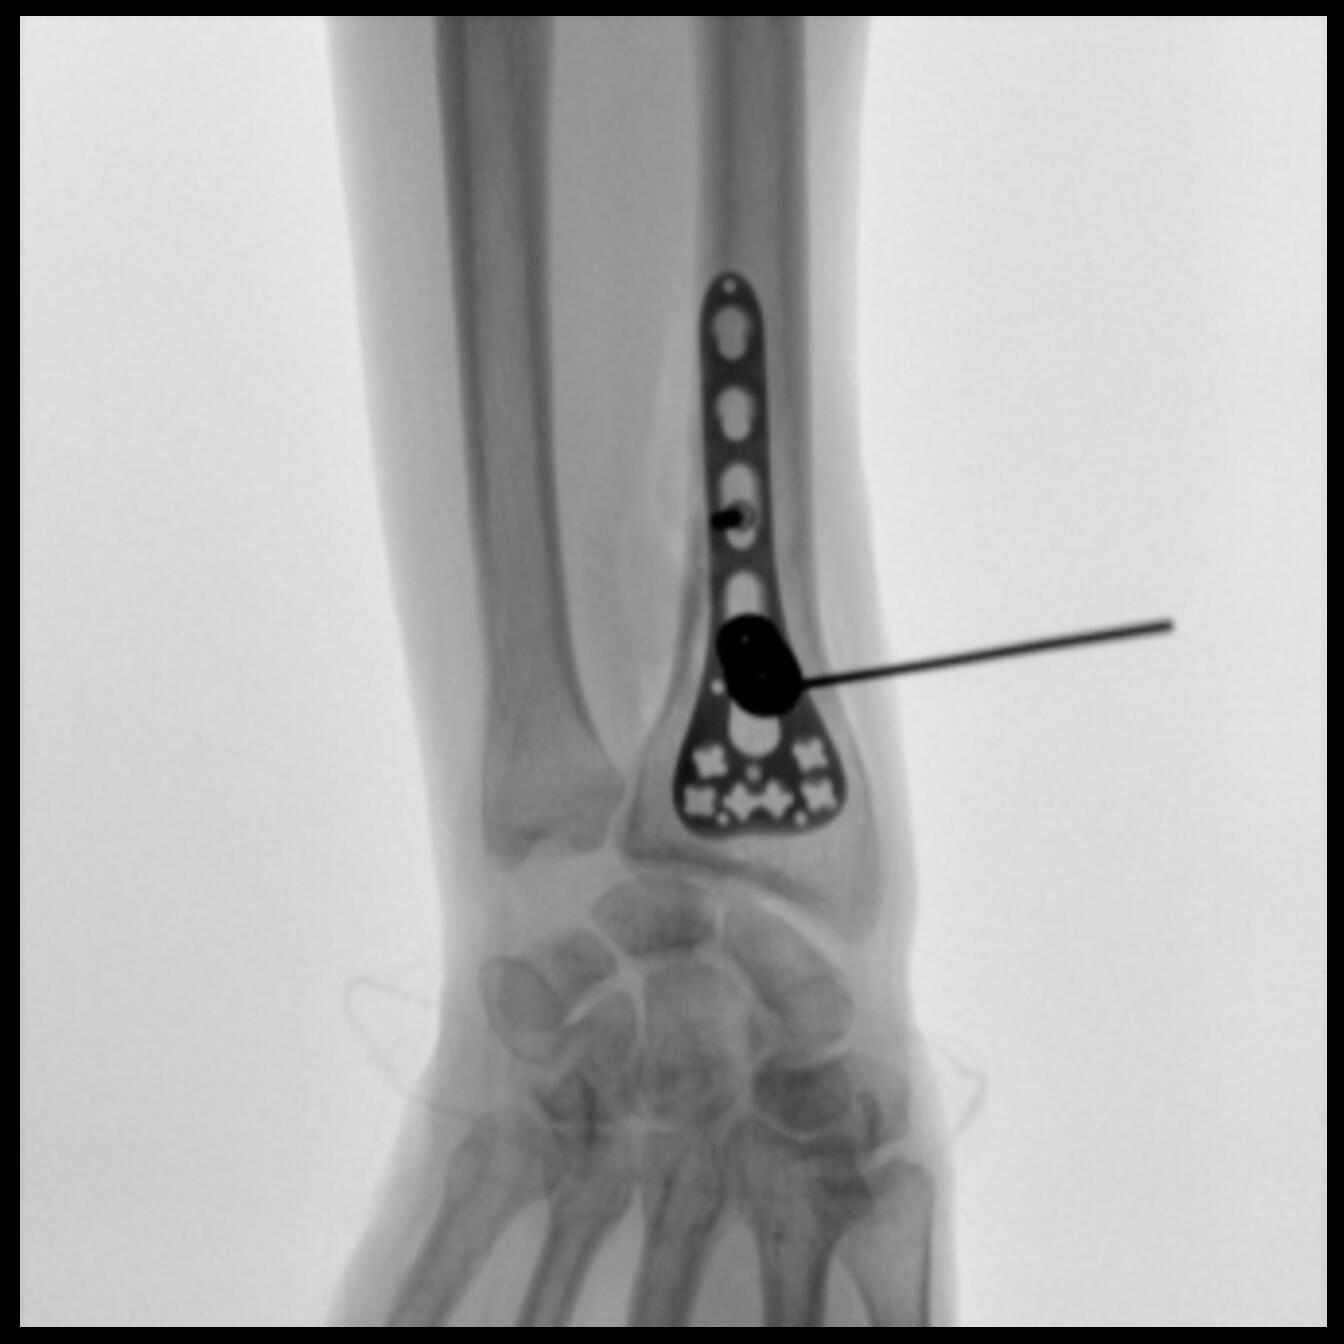

Clinical picture

臨床圖片

配備了兩種平板尺寸,大尺寸動態(tài)平板探測器成像面積較傳統(tǒng)平板探測器提升了25%以上,在視野需求大的手術(shù)中,便于醫(yī)生更好定位病灶點(diǎn),規(guī)劃手術(shù)方案,減少因視野范圍不足而多次透視、點(diǎn)片造成的不便。